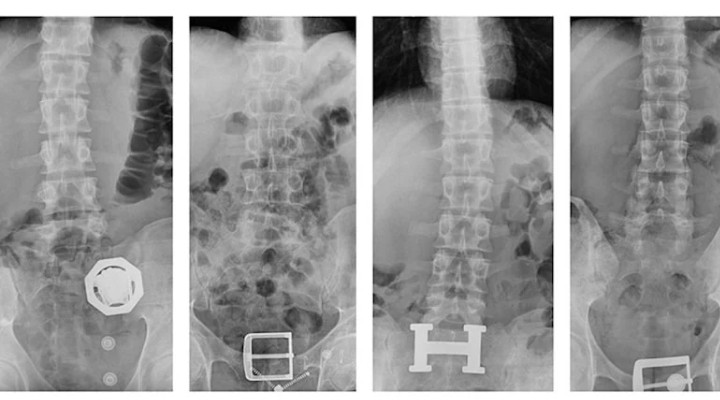

4 şüphelinin çekilen röntgenlerinde midelerinde 121 parça halinde 840 gram eroin tespit edildi. Uyuşturucular, yapılan tedavinin ardından çıkarıldı.